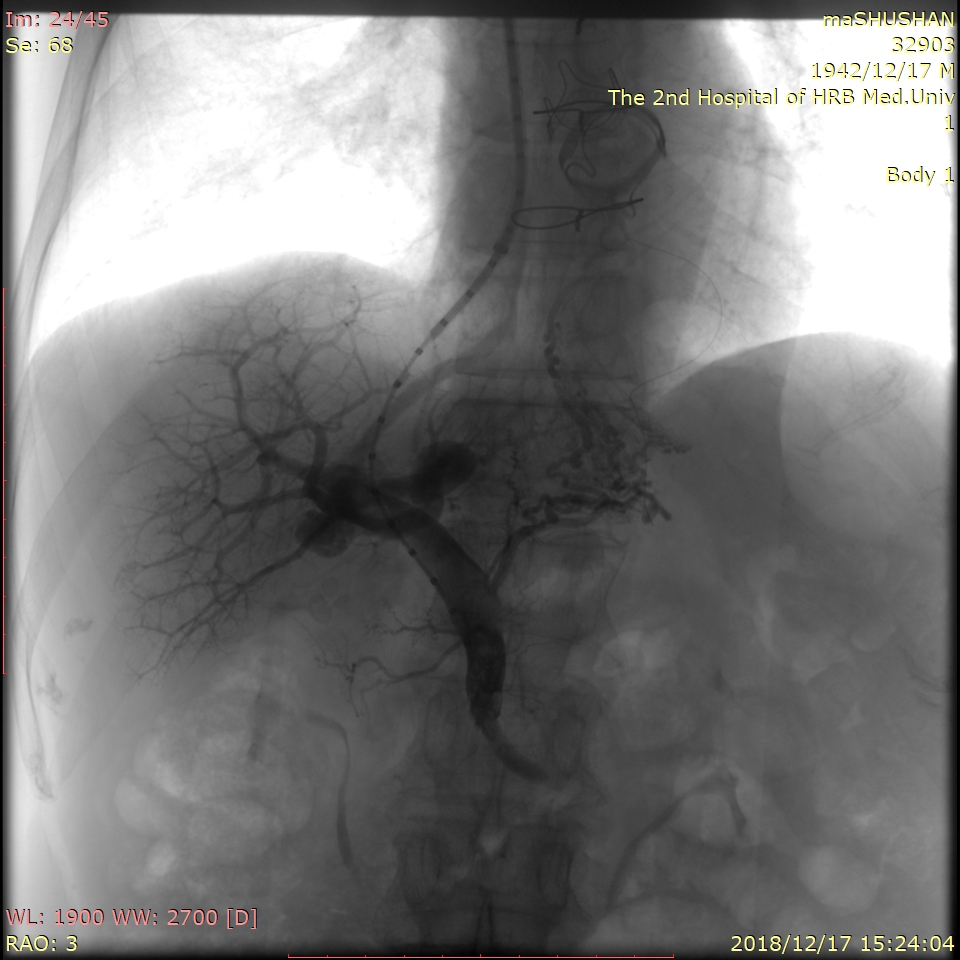

术中将“猪尾”造影导管进入门静脉主干内,造影显示门静脉系统

经过多次的研究讨论患者病情及充分的术前准备,白彬教授和王凯冰副主任医师为马大爷进行了TIPS手术。术中,白彬教授在患者的右侧颈部的静脉为穿刺入口,将导管置入肝门静脉内,经过测量患者门静脉压力达到31cmH2O,比正常人高出一倍;当白彬教授将支架植入肝静脉与门静脉之间建立起人工分流通道后,门静脉压力立即由31cmH2O降为15cmH2O,恢复到正常人的水平,达到彻底治疗目的。整个手术历时约2个小时,仅在马大爷右侧颈部、右侧腹股沟区留下两个3.5mm大小穿刺口。术后患者平安返回病房,继续进行抗感染、保肝、抗凝等治疗,目前,患者术后恢复良好。